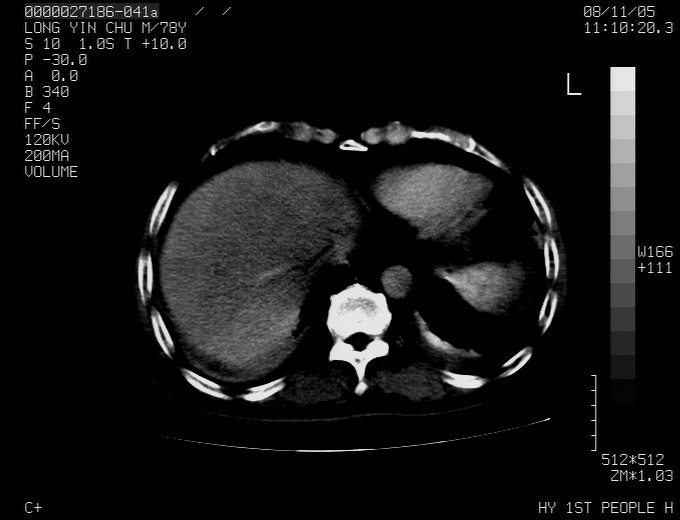

标题: CT16532:M78Y,肝脏病变,请会诊 [打印本页]

标题: CT16532:M78Y,肝脏病变,请会诊

腹胀,腹痛就诊,男性,78岁,外院b超未见异常。

肝ca,脾肾转移

支持脾肾转移瘤,双侧胸腔积液。

考虑弥漫性肝癌并脾及双肾转移.双侧胸水.

图片质量欠佳:多考虑:左侧肾癌。脾脏转移!胸膜转移!

肝脾肾转移瘤可能性大,左肾不除外梗塞,双侧胸水

考虑肝癌并双肾及脾脏转移;双侧胸腔积液。